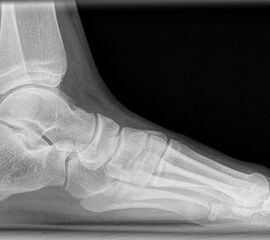

Röntgen

Standard ist die belastete Röntgenaufnahme des Fußes dorso-plantar und seitlich. Günstig ist eine Röhrenkippung von 10°-20°, um die Gelenke der Lisfranc-Linie einsehen zu können.

• Elevation/ Plantarisierung I. Strahl

• Pes metatarsus adductus